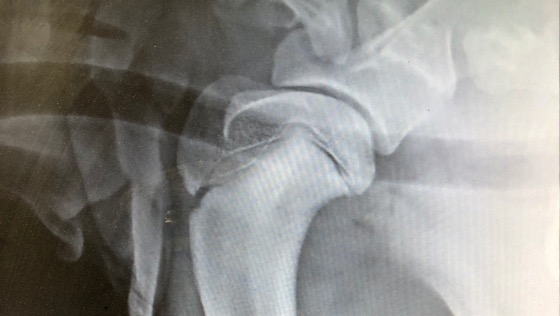

Przyjechała do nas aż z Bośni , była szczęśliwym psiakiem, niestety juz w pierwszych tygodniach pobytu jej zdrowie zaczęło się komplikować. Pierwsze rtg i problemy ze stawami biodrowymi, zabieg zespolenia juz sporo nas kosztował. Cojka była pozbawiona ruchu przez 2 tyg. Była bardzo smutna i przybita. Każdy by był. Kiedy już wszystko wróciło do normy i poczynała swoje pierwsze podrygi zaniepokoiła nas kulawizna na przednia łape. Diagnoza :OCD- osteochondroZa, niestety zajęte obie łapy, plis niepokojace zmiany w dolnuch częściach łapek. Cojka jest od 2 tyg na lekach przeciwbòlowych, niestety nie moze biegać , skakać . Jest smuna , nieszczęśliwa bo bola ja bardzo łapki.